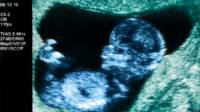

It provides that pregnant women to referral for abortion will be asked to go for ultrasound imaging of the fetus and its heartbeat or listening to the heartbeat of the fetus.

“Studies show that about 80% of refuse abortion, seeing the child on the ultrasound monitor. The experience of those countries where we have introduced visualization listening heartbeat of a child in the womb, suggests that this measure is able to affect the decision of the expectant mother to get rid of the child, “- said Mizulina.